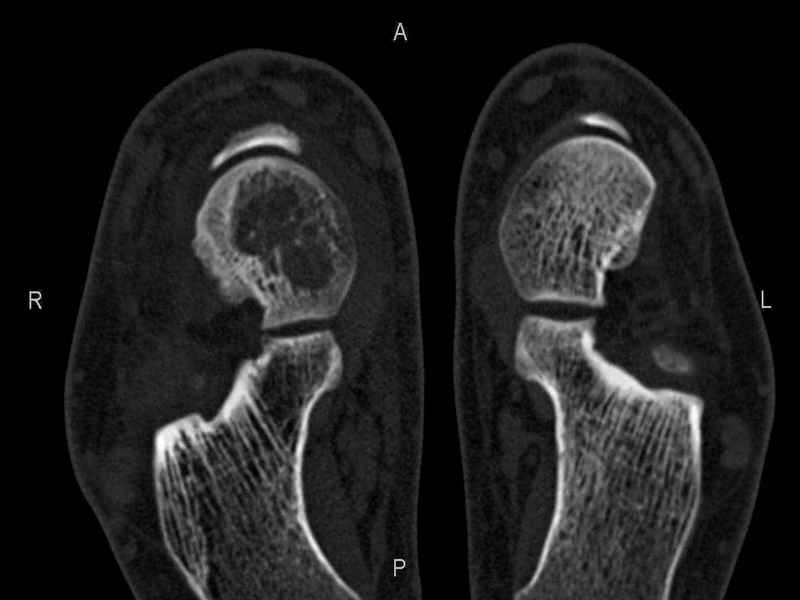

Уважаемые коллеги, обратился за помощью пациент, мужчина, 25 лет. С жалобами на болевой синдром в области голеностопного сустава и среднем отделе стопы. Травму отрицает. Со слов, болевой синдром в течении 1 года. Последние 1-1.5 мес периодически вынужден пользоваться костылями. После ограничения нагрузки боли уменьшаются.Соматически здоров. До появления болей активно занимался рукопашным боем. На СКТ картина рассекающего остеохондрита блока таранной кости, киста шейки таранной кости с признаками импрессии суставной поверхности. А также - разрастания переднего края б\берцовой кости сопровождающиеся клиникой импиджмент синдрома. Предполагаемый план лечения- удаление свободного фрагмента суставного хряща из трансмаллеолярного доступа с рассверливанием поверхности дефекта, кюретаж кисты шейки с заполнением полости биокомпозитом + дебридмент переднего отдела голеностопного сустава. Прошу высказать своё мнение, за и против, предполагаемого плана лечения. А также по возможности ответить на вопросы: 1. Есть ли необходимость в улучшении васкуляризации таранной кости (например подтаранный артродез). 2. Учитывая планируемое применение биокомпозитного цемента целесообразно ли заполнение им дефекта блока таранной кости с моделированием края суставной поверхности.

СТ чётко демонстрирует секвестр, но открыв сустав вероятно, что хрящ тарана окажется интактным и только пальпацией/ ЭОП можно будет

идентифицировать локализацию секвестра. Если вы с этим столкнетесь, то секвестрэктомию я бы предложил сделать не со стороны суставной поверхности тарана, а со стороны угла тарана, субхондрально кюрретаж стенок, разнонаправленную туннелизацию спицей или 1.1мм сверлом и заполнить дефект спонгиозным графтом.